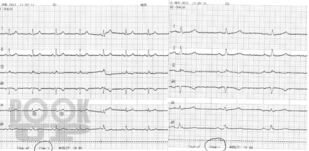

Наглядная ЭКГ

Стаценко И. Ю. Наглядная ЭКГ : учебное пособие / И. Ю. Стаценко, В. С. Сергеев, М. Е. Стаценко. - М. : Логосфера, 2022. - 82 c. - ISBN 9785986570907. - Текст : электронный // ЭБС "Букап" : [сайт]. - URL : https://www.books-up.ru/ru/book/naglyadnaya-ekg-15736724/ (дата обращения: 08.03.2026). - Режим доступа : по подписке.

Учебное пособие по электрокардиографии для студентов-медиков, осваивающих пропедевтику внутренних болезней. Книга учит анализировать ЭКГ, выявлять ключевые патологии: гипертрофии сердца, ишемическую болезнь сердца, аритмии, инфаркт миокарда. Через структурированный материал и тестовые задания формирует профессиональные компетенции: